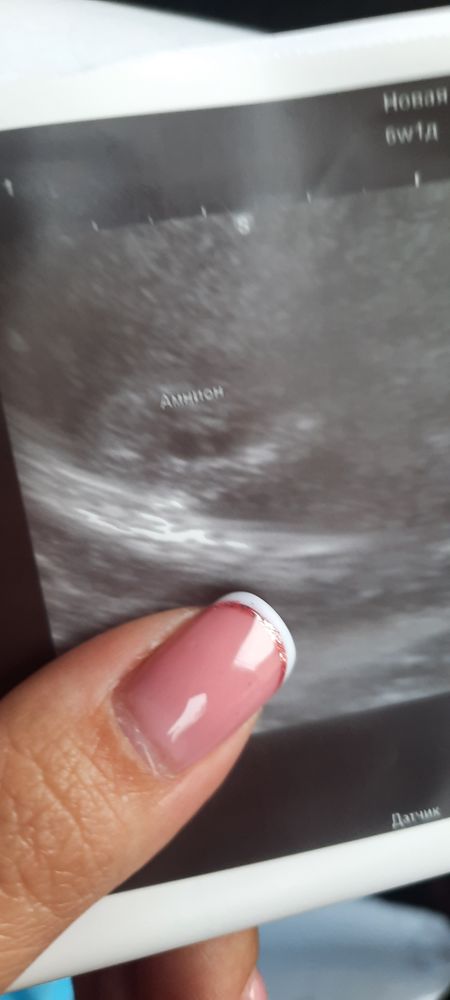

УЗИ 6 недель

УЗИ от 31.08 - плодное яйцо? 3 мм

УЗИ от 06.08 - плодное яйцо 5,6 мм

ПЯ почти не выросло.. вы конечно ещё сдайте хгч.. но ПЯ за 6 дней два миллиметра прибавило, это плохо